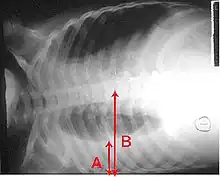

Pleural effusion Anteroposterior Chest X-ray of a pleural effusion. The A arrow shows fluid layering in the right pleural cavity. The B arrow shows the normal width of the lung in the cavity